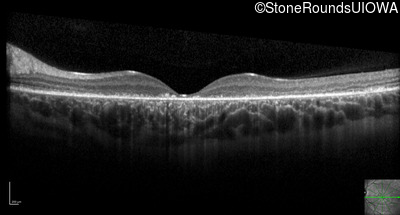

Optical Coherence Tomography - Left - 10/300 sc

Exemplar / OCT Stack